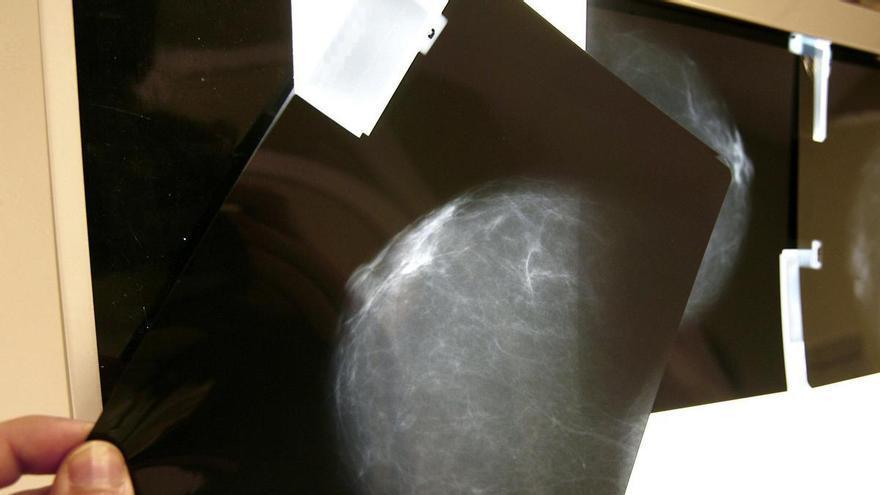

En España la tasa de mortalidad por cáncer de mama ha caído el 41,9 % entre 1990 y 2023, desde los 23,9 fallecimientos por cada 100.000 habitantes en 1990 a trece en 2023, lo que sitúa a España con una de las tasas más bajas de los países desarrollados, por delante de potencias como Estados Unidos, Francia o Alemania.